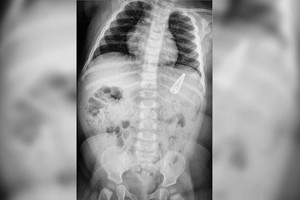

La radiografía está fechada dos horas después, y allí se ve bien que el clip está en el estómago. Con la punta, roma, hacia arriba, y la base hacia abajo, y afilados los bordes metálicos. Fácil era imaginarse que le sería difícil, al clip, salir de allí. Al menos sin dañarle a la nena las delicadas estructuras internas. No obstante, la propuesta fue esperar, y observar.